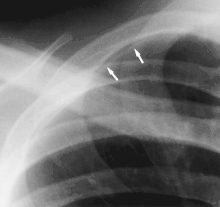

AP radiograph demonstrating companion shadow of the clavicle

A rib companion shadow (indicated by two arrows)

- Rib companion shadows parallel the ribs and measure 1–5 mm in diameter project adjacent to the inferior and inferolateral margins of the first and second ribs and the axillary portions of the lower ribs. These companion shadows of the first and second ribs occur in 35% and 31% of the population, respectively. Rib companion shadows represent the fat and muscles in the intercostal space. The shadows that accompany the ribs may mimic pleural and lung disease.[2]